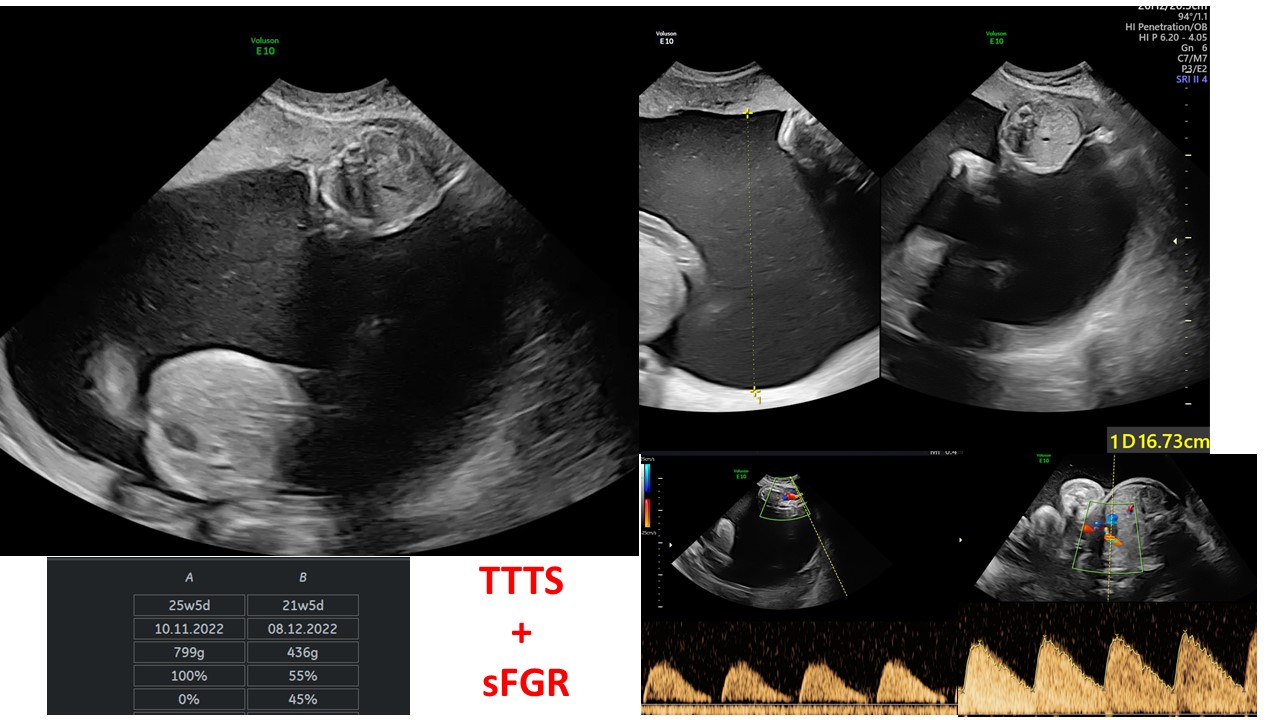

Cập nhật chẩn đoán và xử trí đa thai

BS Hà Tố Nguyên - Trung tâm Y học Bào Thai BV Đa khoa Tâm Anh TPHCM